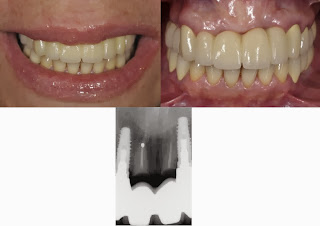

#11 This needs replacemtn to the exact same degree the authors need to write this article. They couldn’t find decay to replace or a broken tooth? I’ll see 100 teeth worse than that by noon on any given day and not even think about touching it. Total over treatment.

#8Pontic site development site for case with low lip line and that would have much better result by lasering tissue, forming an ovate site, and then using ovate pontic. The final results look like nothing was done to preserve anything. All this did was add risk of one of the retained roots blowing up down the road. Bad idea, unwarranted, and bad result. Real tri-fecta!

#7